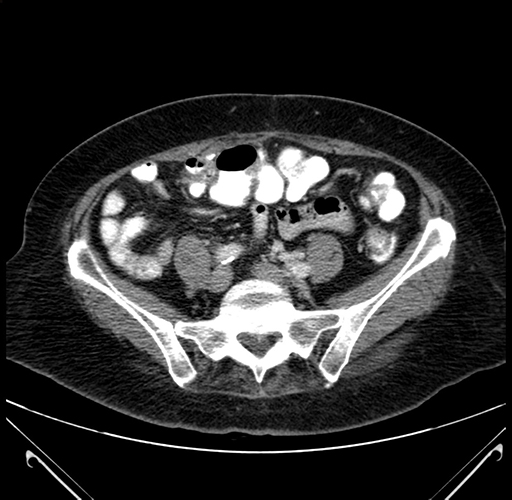

Pre-Chemo: Axial Venous

Axial Venous